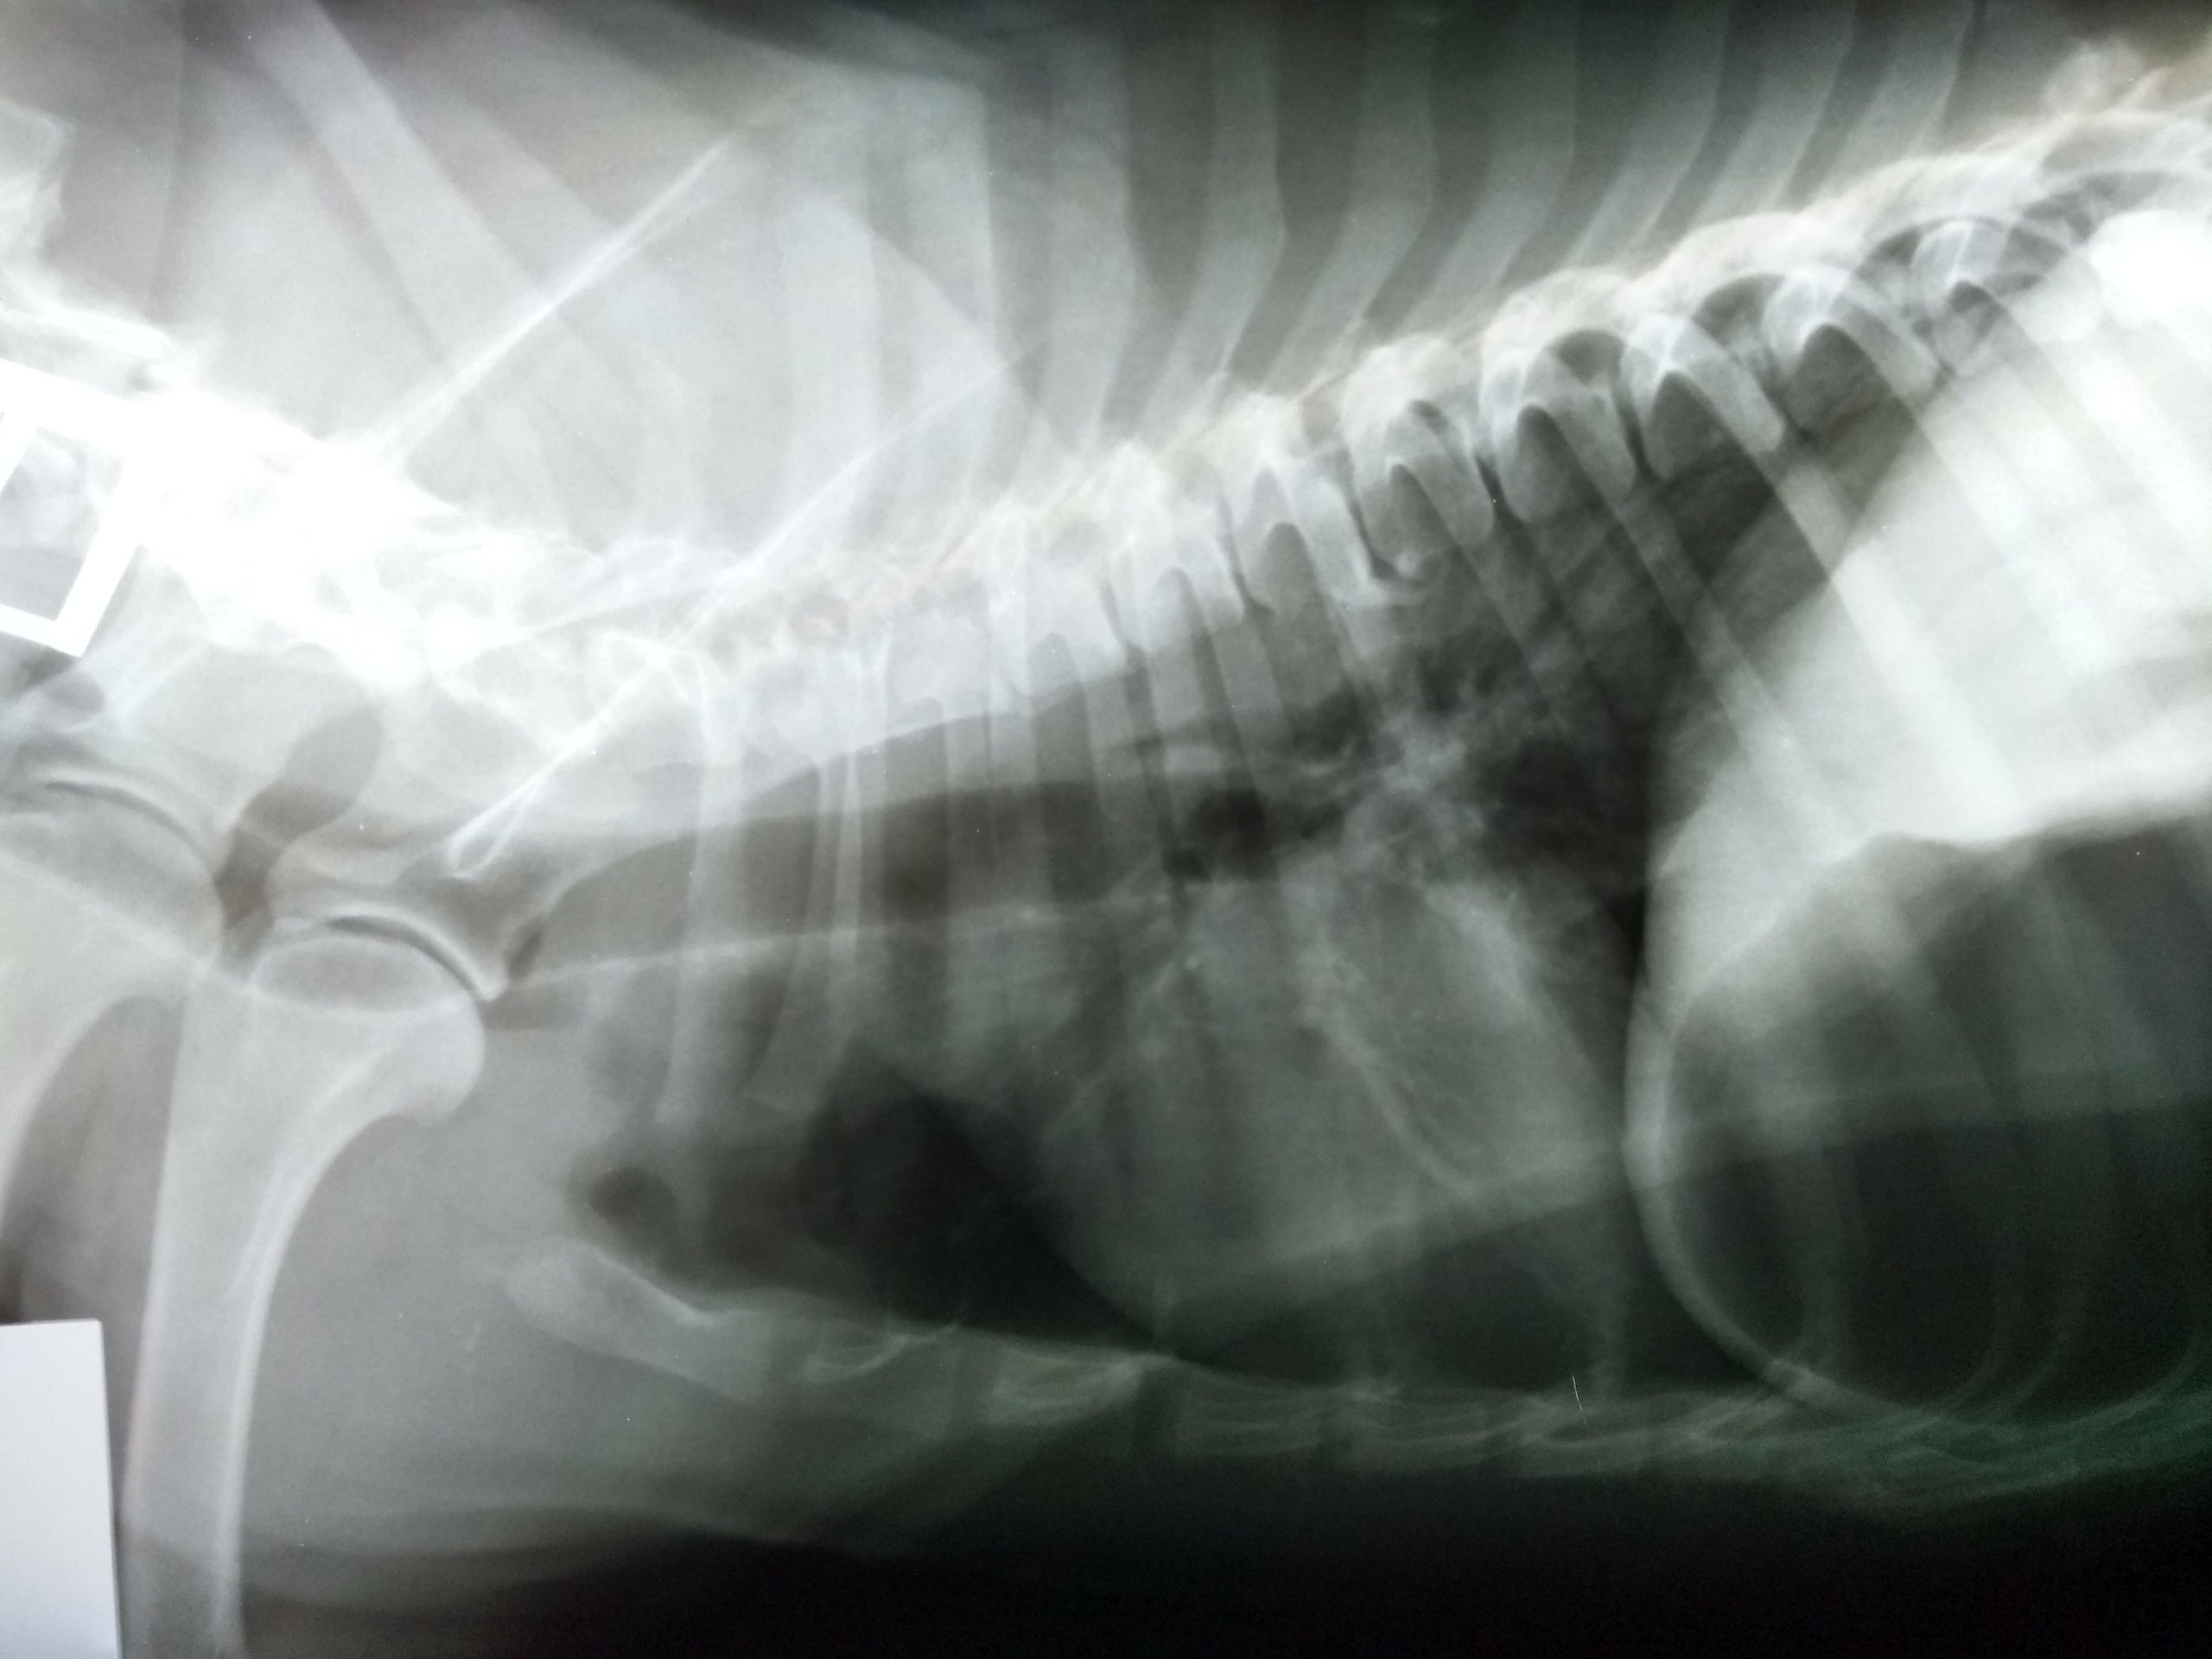

Se realiza estudio radiográfico de tórax y abdominal (no se incluyen todas las radiografías): El estudio no fue concluyente y el veterinario solicita estudio ecográfico abdominal a Dxia.

Radiografía lateral abdominal